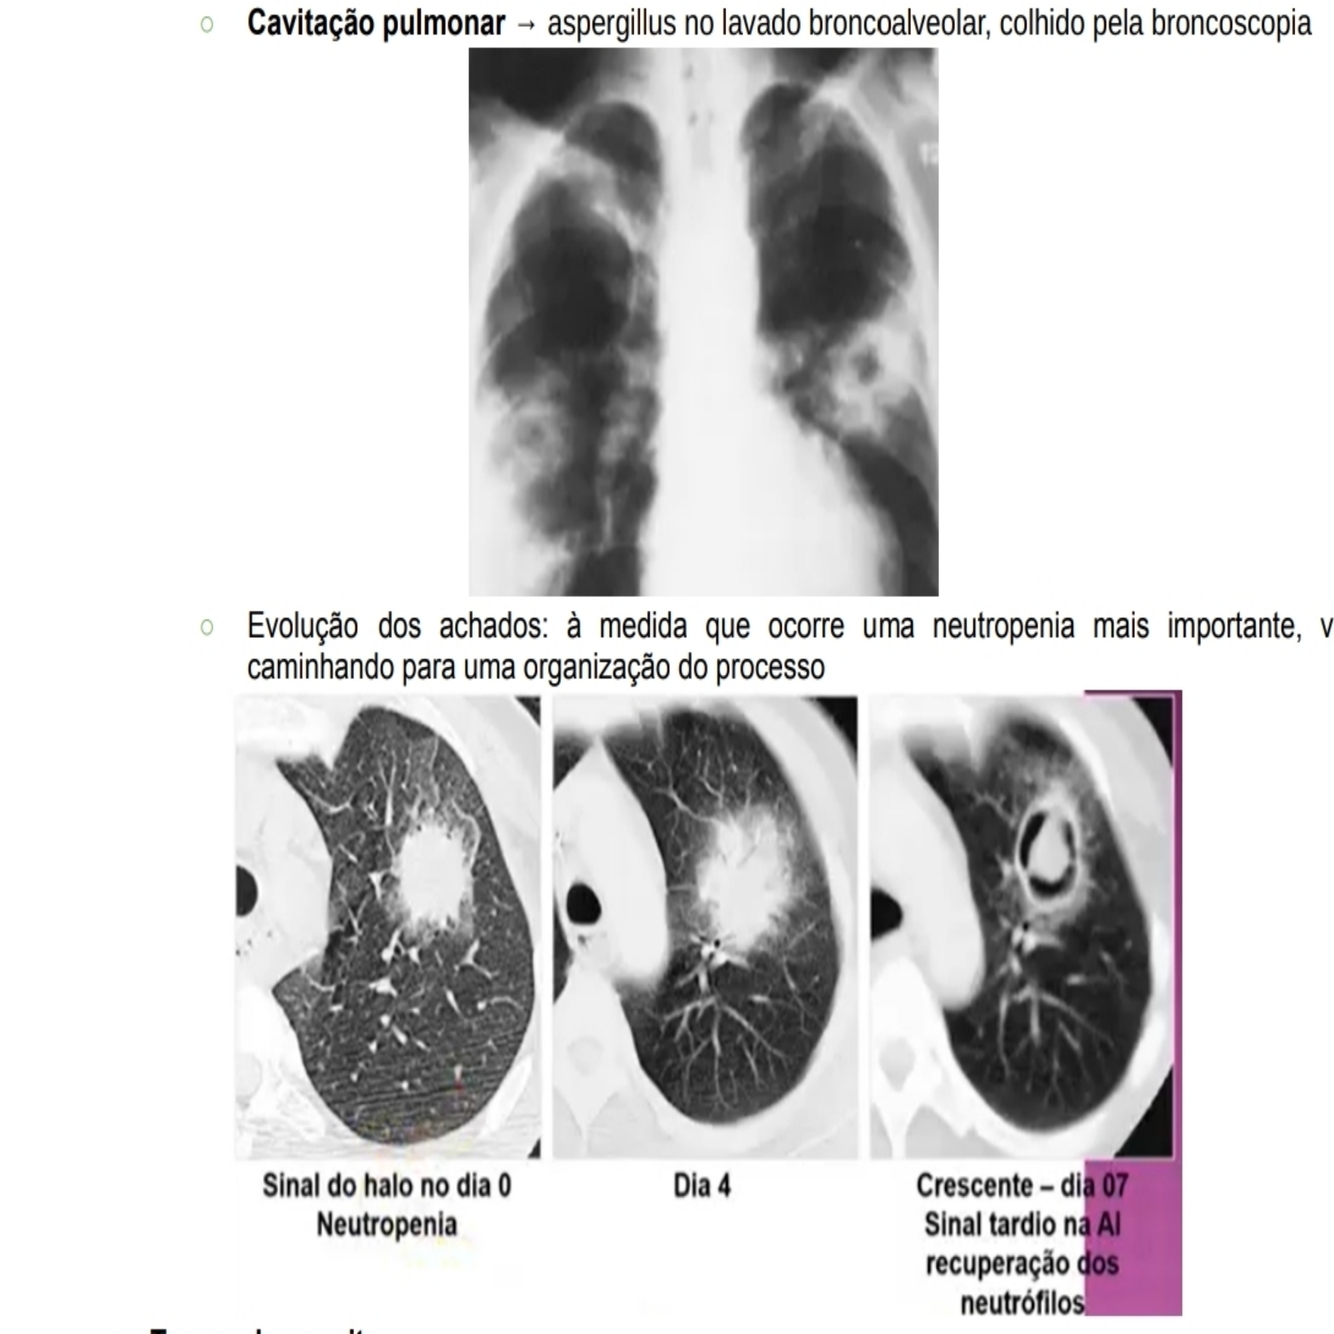

• TC ou Rx mostram infiltrados pulmonares com presença de múltiplos nódulos pulmonares -> nódulos com halo em sua periferia (sinal do halo) -> evolução com extensas áreas de necrose do parênquima pulmonar